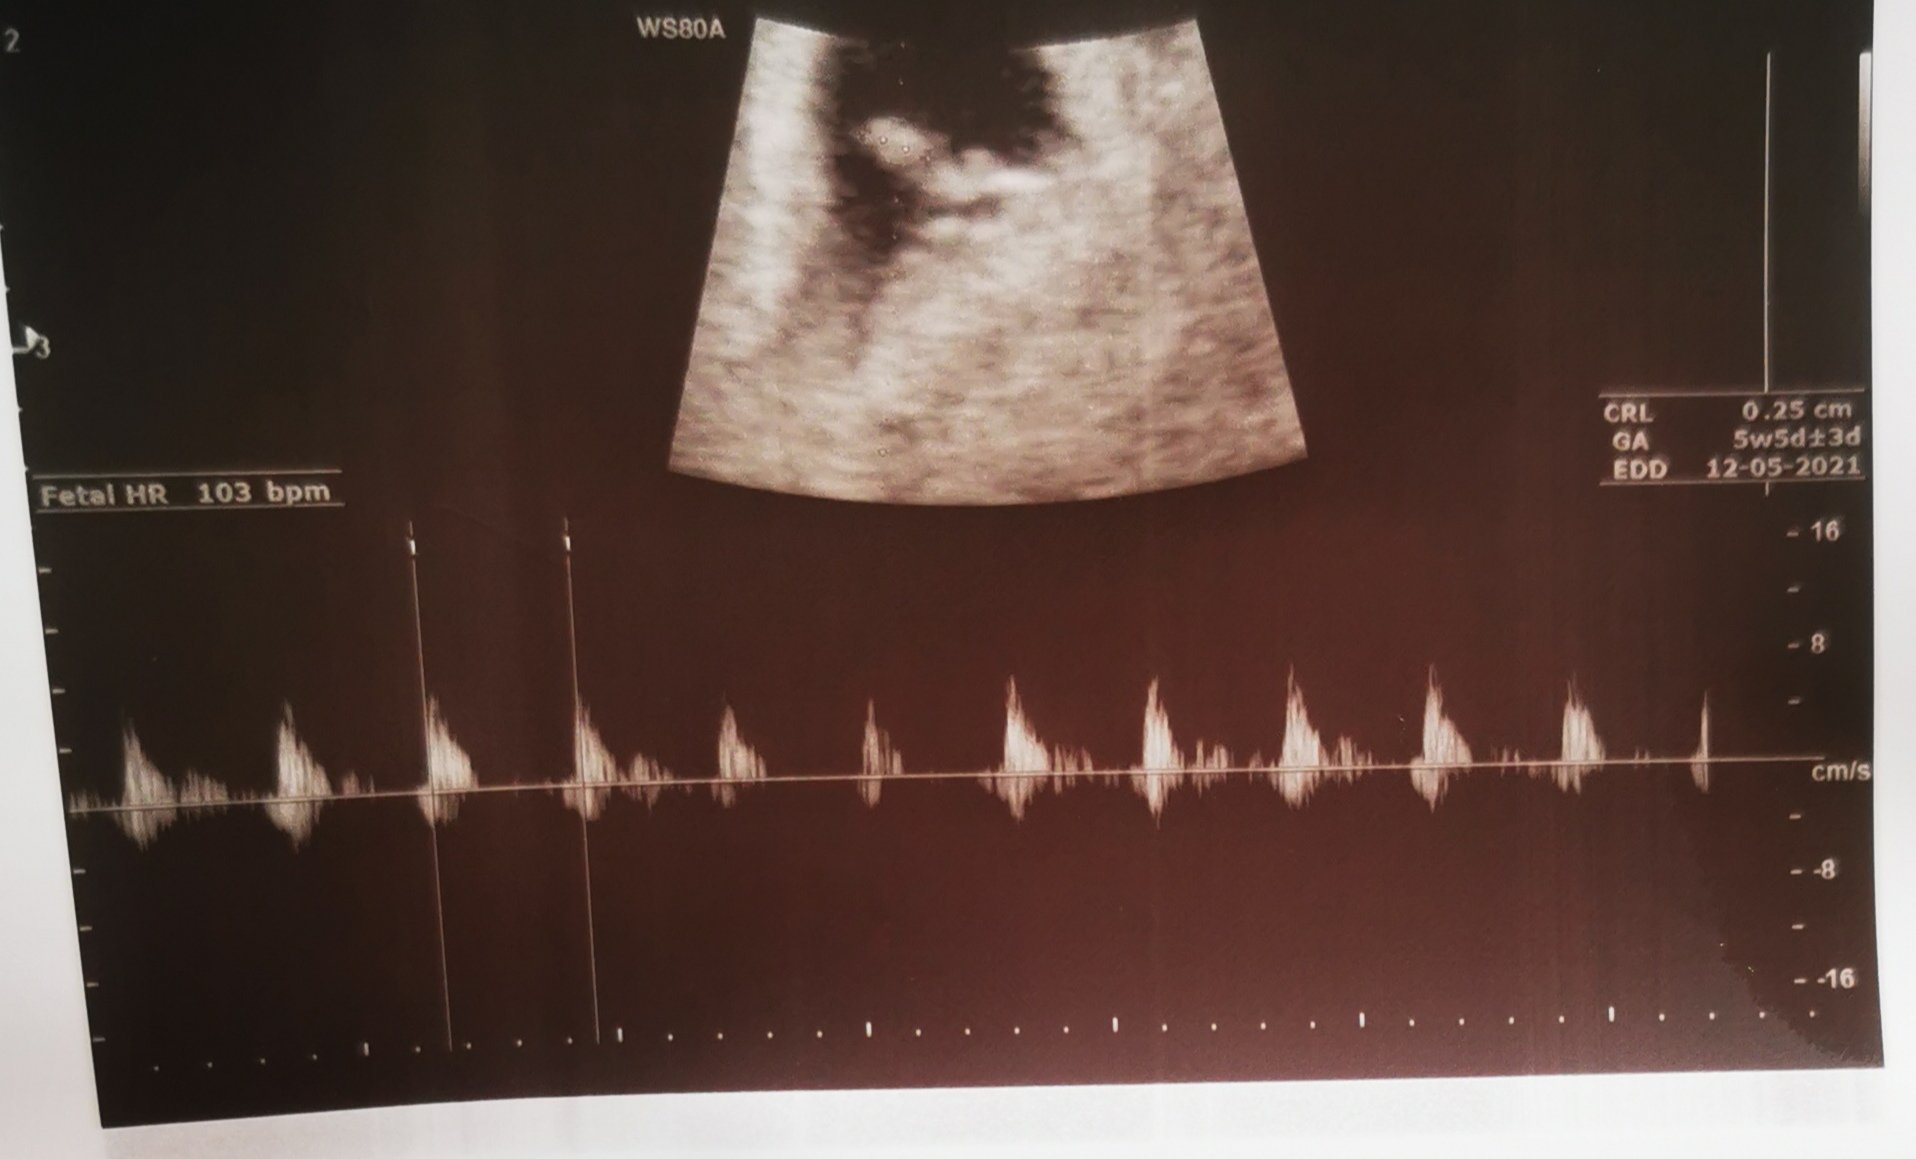

Не, 5с 5д (горе в ляво). Толкова съм по МЦ и съм с О след 16 ден Simple Smile Първоначално каза, че няма как да се чуе, но пък се видя, че 'бие' и взе, че се чу сърдечната дейност.

На снимката със сърдечната дейност е 5с5д